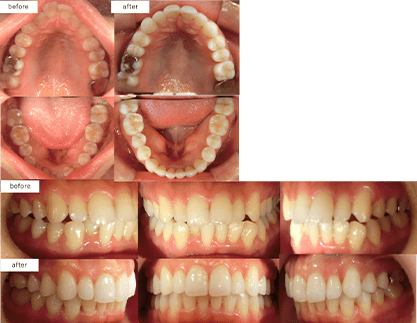

治療方法 マウスピース型矯正装置

(インビザライン)

光加速装置「PBMヒーリング」治療の説明 主訴:空隙 年齢 28歳 ![]()

抜歯箇所 左上下8抜歯、右下8抜歯 治療費用 877,800円

(相談・検査・診断料 無料、調整料 無料)治療期間 6ヶ月 通院回数 10回 治療の内容・詳細 カスタムメイドで制作されたマウスピースを定期的に交換しながら少しずつ歯に適切な力をかけて歯並びを整えていく矯正治療です。 治療の副作用(リスク) 装着時間が少ないと治療期間が長引く可能性があります。

他の矯正治療法と同様に、疼痛・歯根吸収・歯肉退縮の可能性や適切な保定をしないと治療後に後戻りすることがあります。